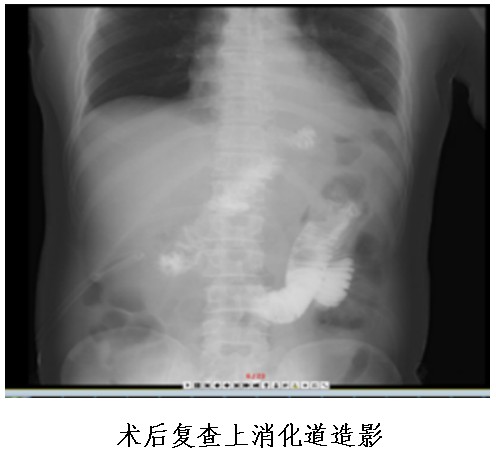

①食管空腸吻合口;

②殘胃空腸吻合口;

③空腸空腸吻合口。

其中,食管空腸吻合口距殘胃空腸吻合口15-20cm,殘胃空腸吻合口距空腸空腸吻合口15—20cm。

食物通過食管空腸吻合口后,一部分通過胃空腸吻合口進(jìn)入遠(yuǎn)端胃、十二指腸及小腸,另一部分食物直接進(jìn)入小腸,故稱之為“雙通道”消化道重建。

該吻合方式通過增加了一個殘胃與小腸的食物通道,可以防止胃酸直接反流進(jìn)入食管,而遠(yuǎn)端胃和原有消化通道的保留,可以維持胃與十二指腸的部分功能,成功解決近端胃切除術(shù)后患者胃食管返流、胃癱及遠(yuǎn)期營養(yǎng)障礙的問題,大大提高術(shù)后患者的生活質(zhì)量。